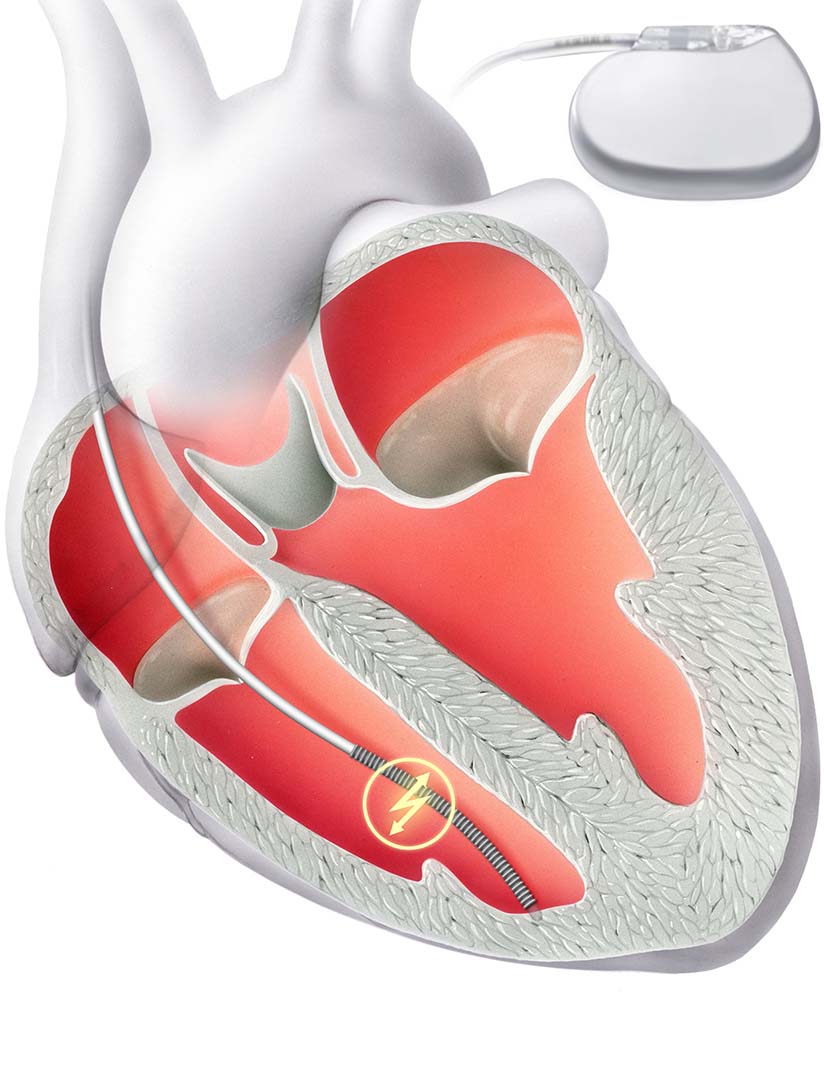

Bei hohen Risiko für lebensbedrohliche Herzrhythmusstörungen kann die Implantation eines internen Schockgerätes (ICD) notwendig sein. Der ICD wird ähnlich wie ein Herzschrittmacher in örtlicher Betäubung implantiert.

Der Defibrillator überwacht den Herzrhythmus kontinuierlich und erkennt einen schnellen und lebensbedrohlichen Herzrhythmus. In diesem Fall kann er mittels Überstimulation oder Abgabe eines elektrischen Schocks den normalen Herzrhythmus wiederherstellen.

Ähnlich wie ein Schrittmacher besteht der Defibrillator aus zwei Komponenten: Zum einen aus einer Elektrode, die über die Vene in der rechten Herzkammer verankert wird. Zum anderen aus einem Gerät samt Batterie, welches unter die Haut implantiert wird.

Bei der Standard ICD-Therapie wird eine Elektrode direkt ins Herz implantiert. Sie ist Teil eines Defibrillators, der bei zu schnellem Herzschlag den Rhythmus normalisieren kann.

Bei hohen Risiko für lebensbedrohliche Herzrhythmusstörungen kann die Implantation eines internen Schockgerätes (ICD) notwendig sein. Der ICD wird ähnlich wie ein Herzschrittmacher in örtlicher Betäubung implantiert.

Der Defibrillator überwacht den Herzrhythmus kontinuierlich und erkennt einen schnellen und lebensbedrohlichen Herzrhythmus. In diesem Fall kann er mittels Überstimulation oder Abgabe eines elektrischen Schocks den normalen Herzrhythmus wiederherstellen.

Ähnlich wie ein Schrittmacher besteht der Defibrillator aus zwei Komponenten: Zum einen aus einer Elektrode, die über die Vene in der rechten Herzkammer verankert wird. Zum anderen aus einem Gerät samt Batterie, welches unter die Haut implantiert wird.

Bei der Standard ICD-Therapie wird eine Elektrode direkt ins Herz implantiert. Sie ist Teil eines Defibrillators, der bei zu schnellem Herzschlag den Rhythmus normalisieren kann.